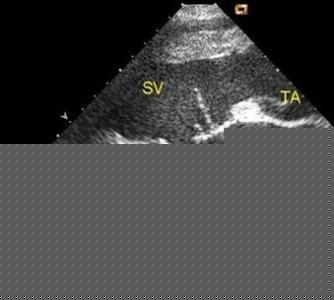

3三是要做超聲心動圖檢查。有先天性心髒病史或曾生育過先天性心髒病的女性,再懷孕的時候應該到醫院做胎兒超聲心動圖,這樣可以查出早期的胎兒是否正常。